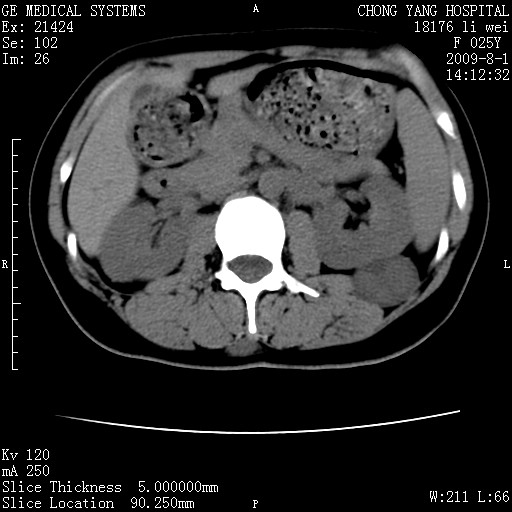

以下是引用pujunzhi在2009-8-1 20:23:00的发言:[br]胸椎旁及背部肌间良性病变,范围广,边界清,沿肌间生长,考虑淋巴管瘤、血管瘤,建议增强扫描。